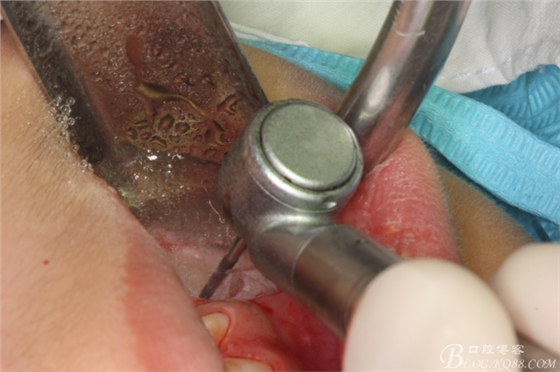

圖5.高速牙鉆去骨